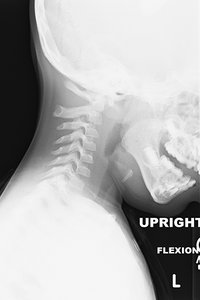

Review the cervical flexion radiograph in Figure 1A. The patient has an increased atlantodental interval (ADI) at C1-C2. Now review the cervical extension radiograph of the same patient in Figure 1B. The ADI decreased. Why?

Figure 1A